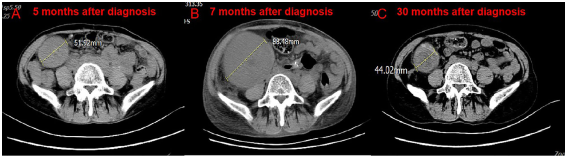

在与患者本人及其家属讨论后,给予第三疗程纳武单抗,同时定期进行血液透析。在血液透析期间,病人患上了高血压,血压高达200/120mmHg。第三疗程后两周,患者出现左腹痛,体格检查发现左肾可触及。CT扫描显示对免疫治疗有部分反应(图2 A-B),移植肾体积增加(图3 A-B)。由于患者拒绝肾活检,急性排斥反应无法得到证实。患者的体能状态下降。

图3. 移植肾的CT扫描

考虑到患者不能耐受免疫治疗,因此中断抗肿瘤治疗。通过药物治疗,高血压慢慢得到控制。第三疗程后两个月(2019年6月),CT显示免疫治疗完全有效(图2C),移植肾进一步肿胀。第三疗程后4个月(2019年8月),CT扫描显示持续完全缓解,移植肾肿胀比之前小。两个月后停用霉酚酸钠,继续使用他克莫司 0.5 mg 每天两次进行免疫抑制治疗。每三个月进行一次常规CT扫描。第三疗程后23个月(2021年3月),CT证实移植肾肿胀进一步减轻,肾脏恢复到原来的体积(图3C)。未观察到复发(图2D)。患者仍依赖血液透析。